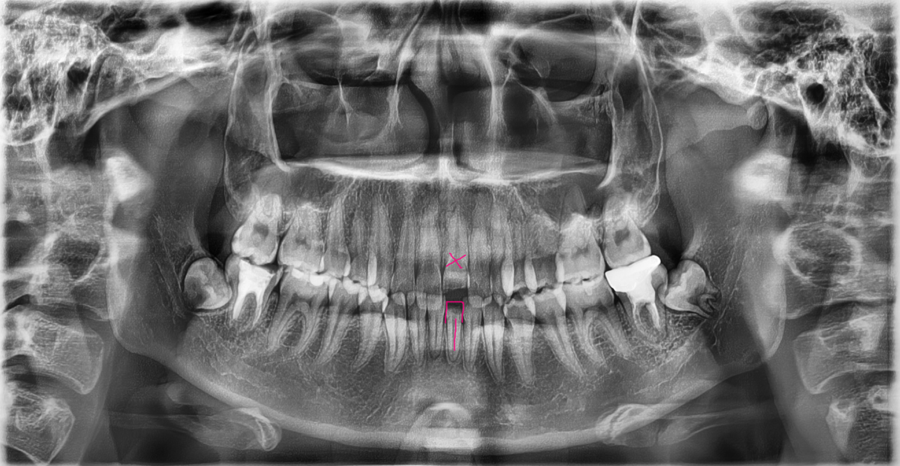

This is an X-ray of a patient who visited after a traffic accident with about half of the front tooth broken.

At first glance, the fractured area may seem to be the only problem,

but this was a case in which the tooth root and the surrounding jawbone also needed to be checked.